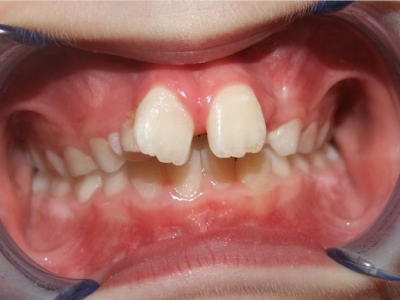

Leeftijd bij aanvang: 9 jaar

1-6 Bonded Hyrax + volledig vast onderkaak + TransForce onderkaak

7-13 Twin Block

14-28 volledig vast onder- en bovenkaak + rotator

Retentie: Wrap-Around

Leeftijd bij retentie: 12 jaar